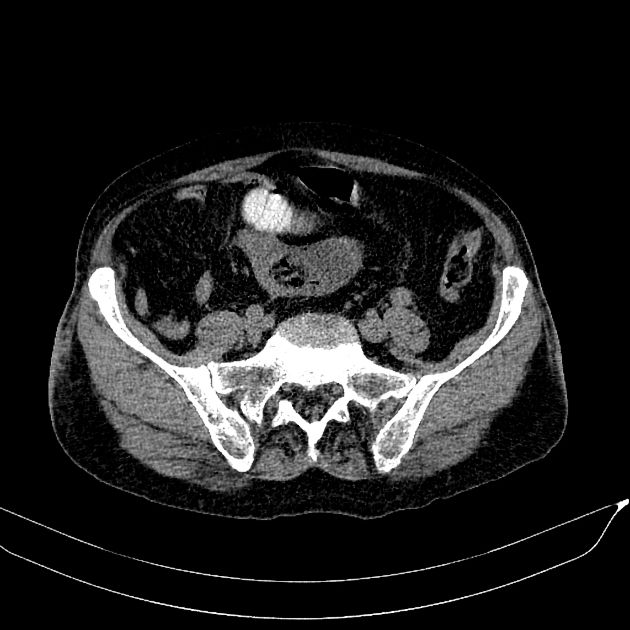

Bezoars

» Thông tin: Nam giới – 80 tuổi.

» Lâm sàng: Đau bụng / Nôn.

# Tắc ruột non do bã thức ăn.